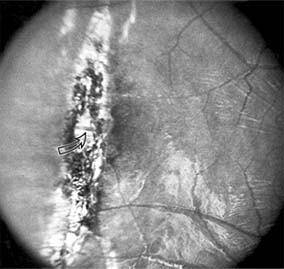

Nonexudative age-related macular degeneration is characterized by variable degrees of atrophy and degeneration of the outer retina, retinal pigment epithelium, Bruch's membrane and choriocapillaris. Of the ophthalmoscopically visible changes in the retinal pigment epithelium and Bruch's membrane, drusen are the most typical (Figure 10-1). Drusen are discrete, round, yellow-white deposits of variable size beneath the pigment epithelium and are scattered throughout the macula and posterior pole. With time, they may enlarge, coalesce, calcify, and increase in number. Histopathologically, most drusen consist of focal collections of eosinophilic material lying between the pigment epithelium and Bruch's membrane; they therefore represent focal detachment of the pigment epithelium. In addition to drusen, clumps of pigment irregularly dispersed within depigmented areas of atrophy may progressively appear throughout the macula. The level of associated visual impairment is variable and may be minimal. Fluorescein angiography demonstrates irregular patterns of retinal pigment epithelial hyperplasia and atrophy. Electrophysiologic testing in most patients is normal.

Figure 10-1

Figure 10-1: Age-related macular degeneration with discrete (small arrow) and large confluent (large arrow) macular drusen.